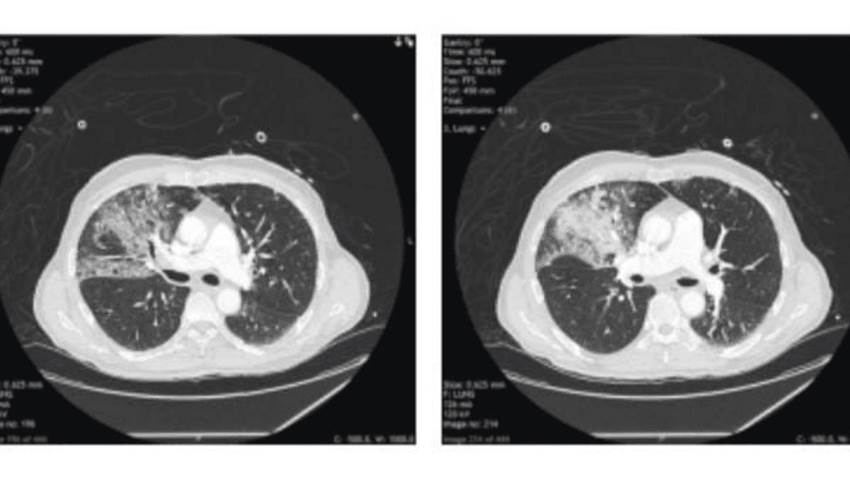

Se registra neumotórax espontáneo a tensión como complicación del COVID-19

El neumotórax a tensión se trata de la acumulación de aire en el espacio pleural bajo presión, junto a la compresión de los pulmones y la disminución...